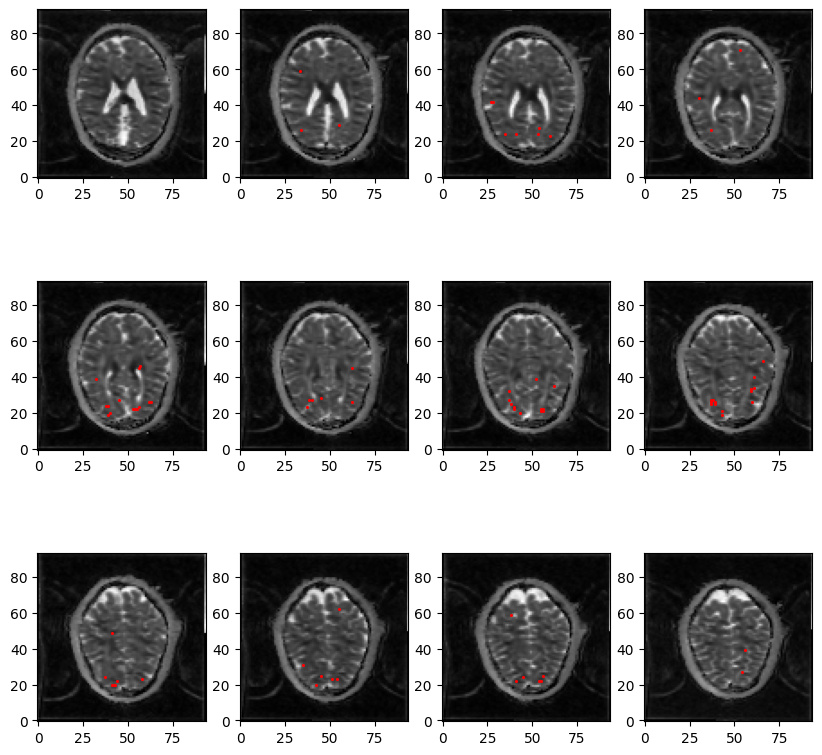

Fig2: Example of WM significant voxels (with z-statistic > 3.1) in red overlaid on an ADC map, in one subject at 3T. While the sensitivity is low, some clusters of voxels can be identified, particularly along the visual pathway stemming from the visual cortex.